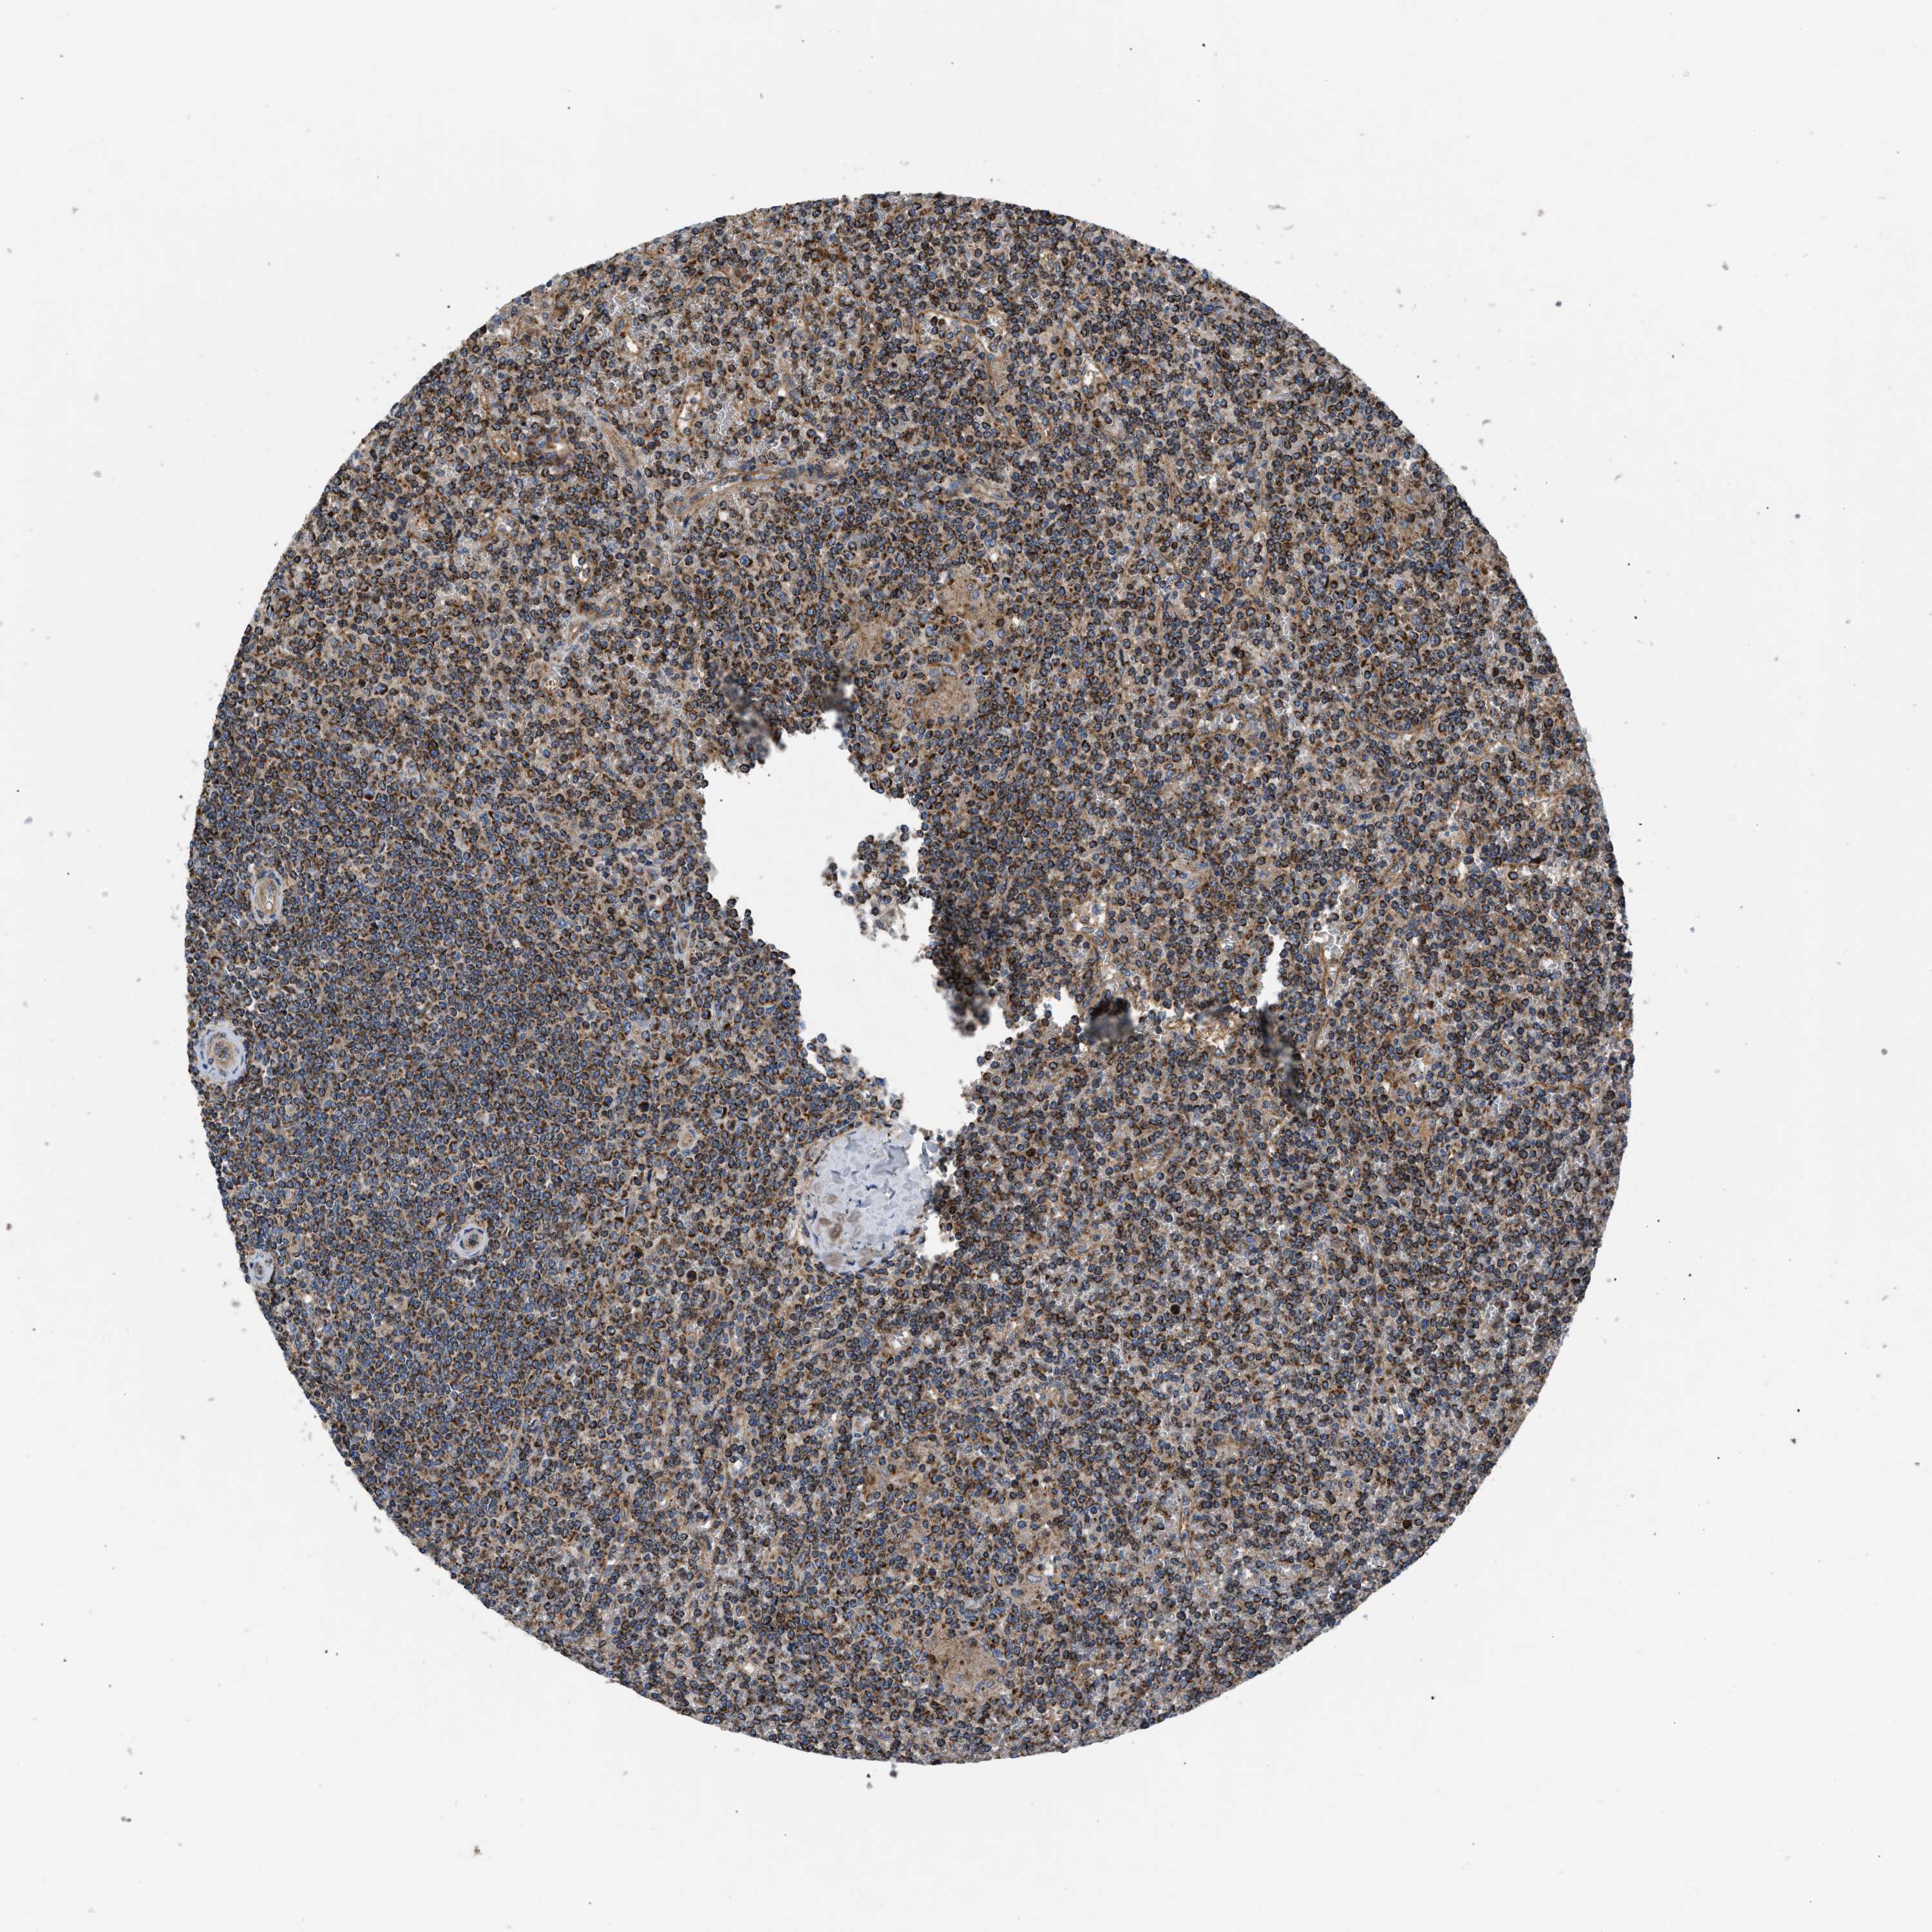

CANCER LYMPHOMA Show tissue menu

LYMPHOMA - Protein expressioni

A mouse-over function shows sample information and annotation data. Click on an image to view it in a full screen mode. Samples can be filtered based on level of antibody staining by selecting one or several of the following categories: high, medium, low and not detected. The assay and annotation is described here.

Each image is clickable and will lead to virtual microscopy that enables deeper exploration of all samples and also displays staining intensity scores, fraction scores and subcellular localization as well as patient and tissue information for each sample.

Antibody HPA003279

Antibody HPA003360

Antibody CAB019303

Malignant lymphoma, non-Hodgkin's type, High grade

Malignant lymphoma, non-Hodgkin's type, Low grade

Hodgkin's disease, NOS